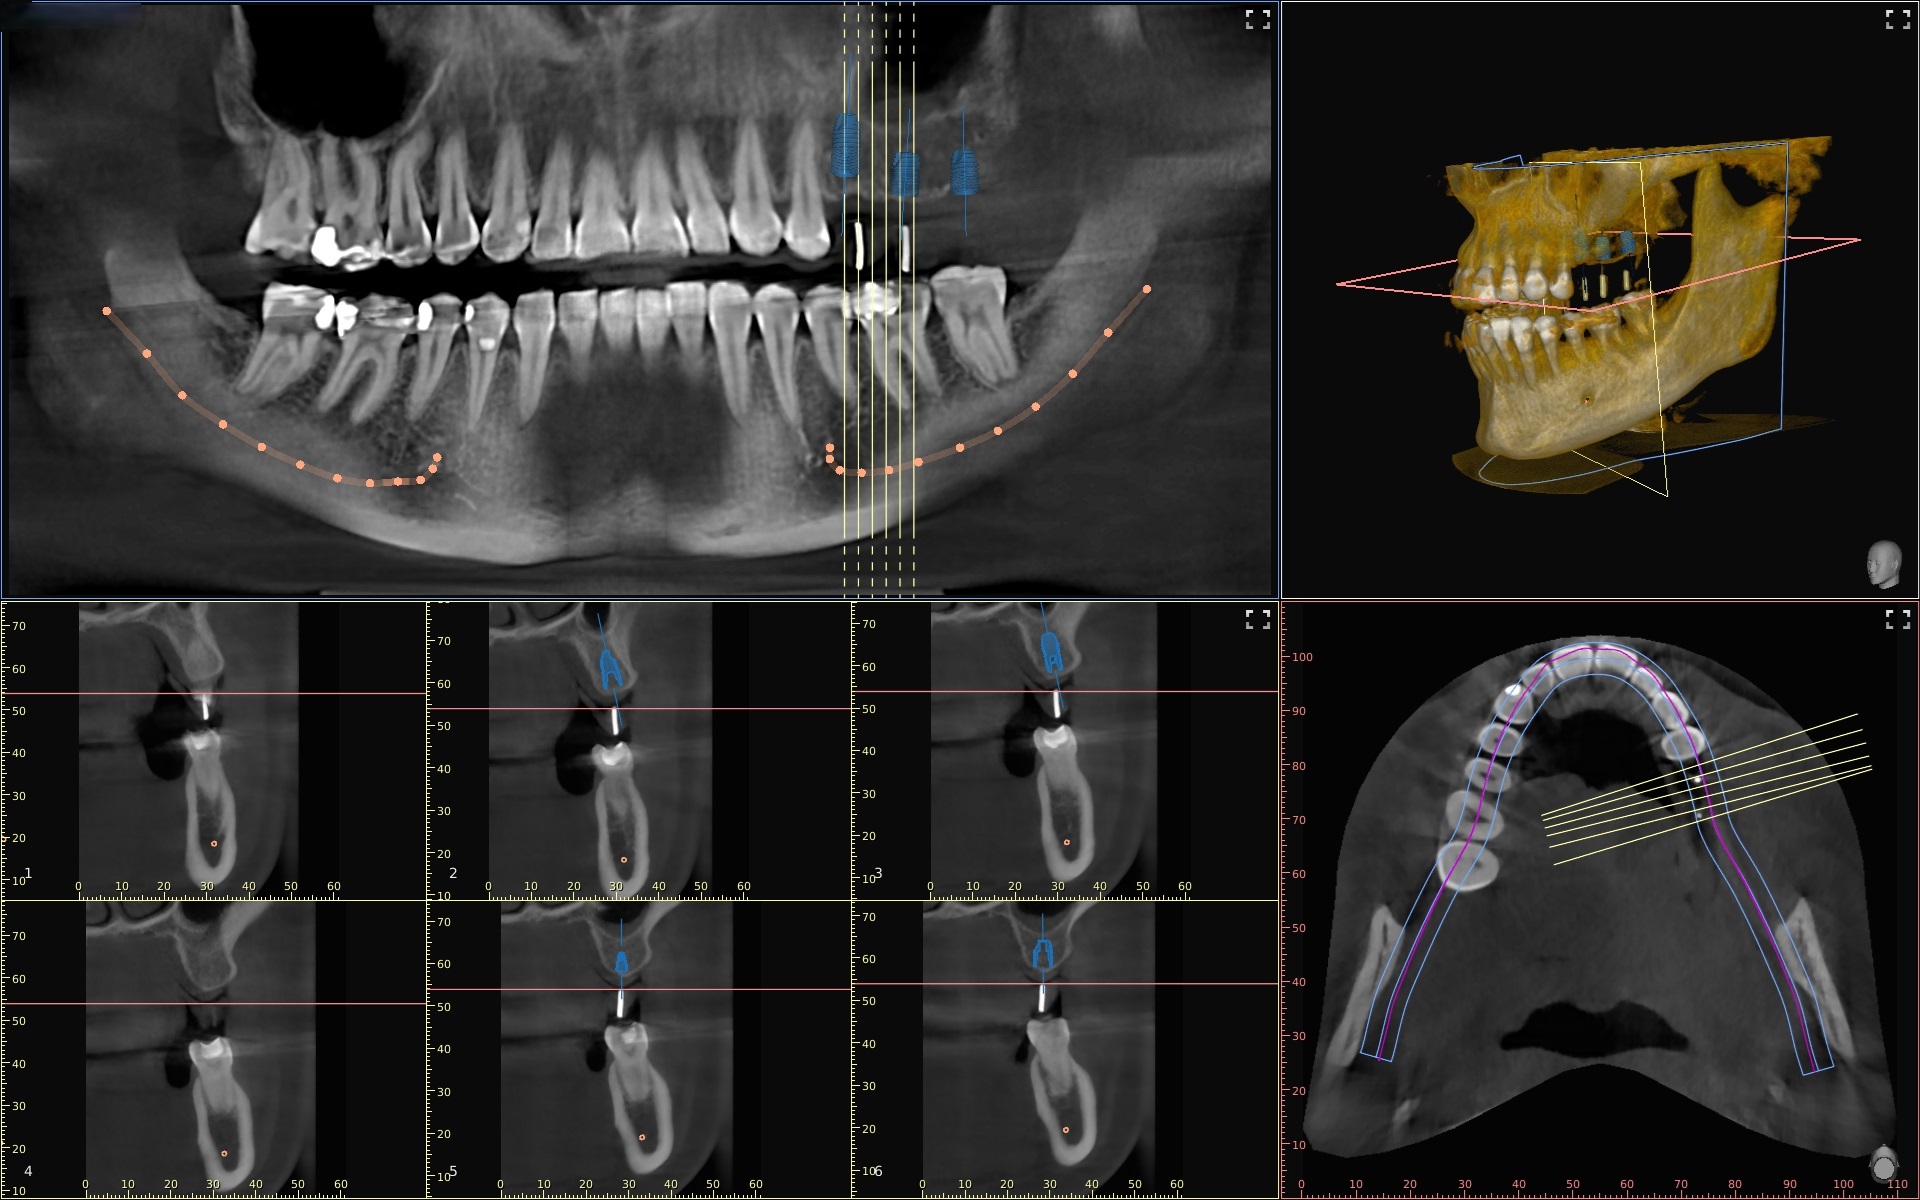

Die Digitale Volumentomographie (DVT) ist ein radiologisches bildgebendes Verfahren, das die Anatomie der Zähne, der Kiefer und des Gesichtsschädels dreidimensional darstellt und dadurch einen bedeutenden Beitrag zur präoperativen Diagnostik leistet.

Hinsichtlich des diagnostischen Wertes kann sie als strahlenreduzierte Variante der aus der Medizin bekannten Computertomographie (CT) gesehen werden. Sie findet besonders Anwendung im Bereich der zahnärztlichen Chirurgie und Implantologie, da sie weniger Störschatten (Röntgenartefakte) durch Metall produziert als die Computertomographie, was besonders im Hinblick auf die oft aus Metall gefertigten zahnärztlichen Kronen und Brücken ein entscheidender Vorteil ist.

Im Vergleich zu den konventionellen 2 D Röntgenaufnahmen, wie dem OPG oder dem Zahnfilm, gibt das DVT dreidimensionale Informationen und dies überlagerungs- und verzerrungsfrei. So kann exakt die Lage eines Weisheitszahnes in Bezug auf wichtige anatomische Strukturen, wie z.B. einen knöchernen Kanal in dem ein wichtiger sensibler Nerv im Unterkiefer verläuft oder die Kieferhöhle beurteilt werden.

Auch im Hinblick auf entzündliche Prozesse oder Fremdkörpersuche, kann deren genaue Lokalisation, ob diese zur Wange oder zum Gaumen liegen, bestimmt werden. Dies liefert wichtige Informationen zur intraoperativen Orientierung, um den operativen Zugang zu bestimmen und gibt zusätzlich Sicherheit und Präzision.